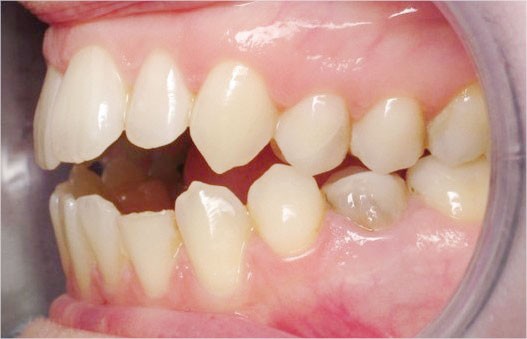

Cas n° 1

Il a été décidé de mettre en œuvre une thérapeutique avec brackets vestibulaires Damon afin d’optimiser l’expansion des arcades, la fermeture de la béance et la réduction du sourire gingival latéral qui perturbe l’esthétique du sourire de la patiente.

La patiente demande des attaches céramiques et nous trouvons un compromis en lui proposant un appareillage Insignia Damon Clear au maxillaire et Damon métallique à la mandibule.